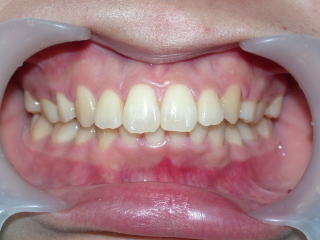

2024年2月20日

術前術後

2022年7月→2024年5月(2年弱でした。これから保定期間に入ります。)